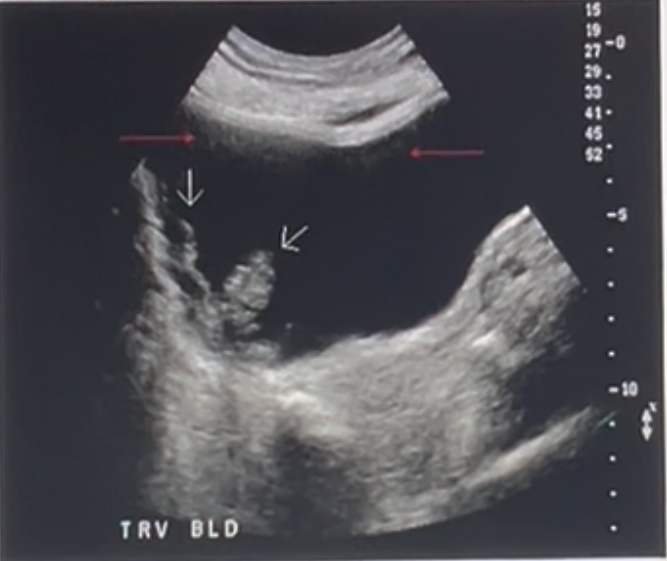

<p>What artifact is demonstrated on the US image by the red arrows?</p><p>a. reverberation<br>b. posterior enhancement <br>c. dirty posterior shadowing<br>d. defocusing</p>

What artifact is demonstrated on the US image by the red arrows?

a. reverberation

b. posterior enhancement

c. dirty posterior shadowing

d. defocusing

posterior enhancement